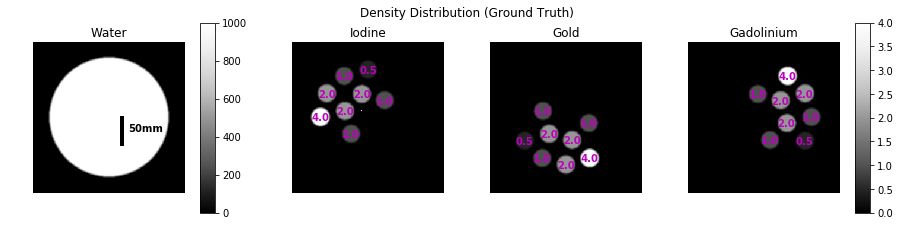

The geometry and sampling conditions for the studies are summarized in Table 1. A digital phantom (Figure 3) of a 100 mm diameter water cylinder and several 15mm diameter cylindrical inserts containing various mixtures of iodine, gold, and gadolinium was employed. The outer ring includes single-contrast inserts of 0.5-4.0 mg/mL concentrations. The inner ring includes mixtures of 1.0 mg/mL and 2.0 mg/mL for all combinations of two materials. The center of the phantom also includes 10.0 mg/mL single voxel impulses of each material for regularization tuning.

Figure 3: Ground truth of the numerical phantom. Magenta text indicates the density in mg/mL of iodine, gold, or gadolinium (corresponding to image subtitle) in cylindrical inserts.